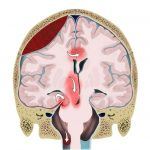

Hộp sọ được chia ra thành những khoang nhờ các nếp gấp màng cứng (dural reflections) của liềm não (falx cerebri) và lều tiểu não (tentorium cerebelli): lều tiểu não tạo thành hố đại não và hố sau, liềm não tạo nên khoang bán cầu đại não phải và trái. Tăng áp lực nội sọ thường dẫn tới thay đổi chêch áp giữa các khoang và dịch chuyển các cấu trúc não. Thoát vị não là sự dịch chuyển cơ học của não, dịch não tủy và mạch máu lớn của não từ khoang này sang khoang khác trong hộp sọ…